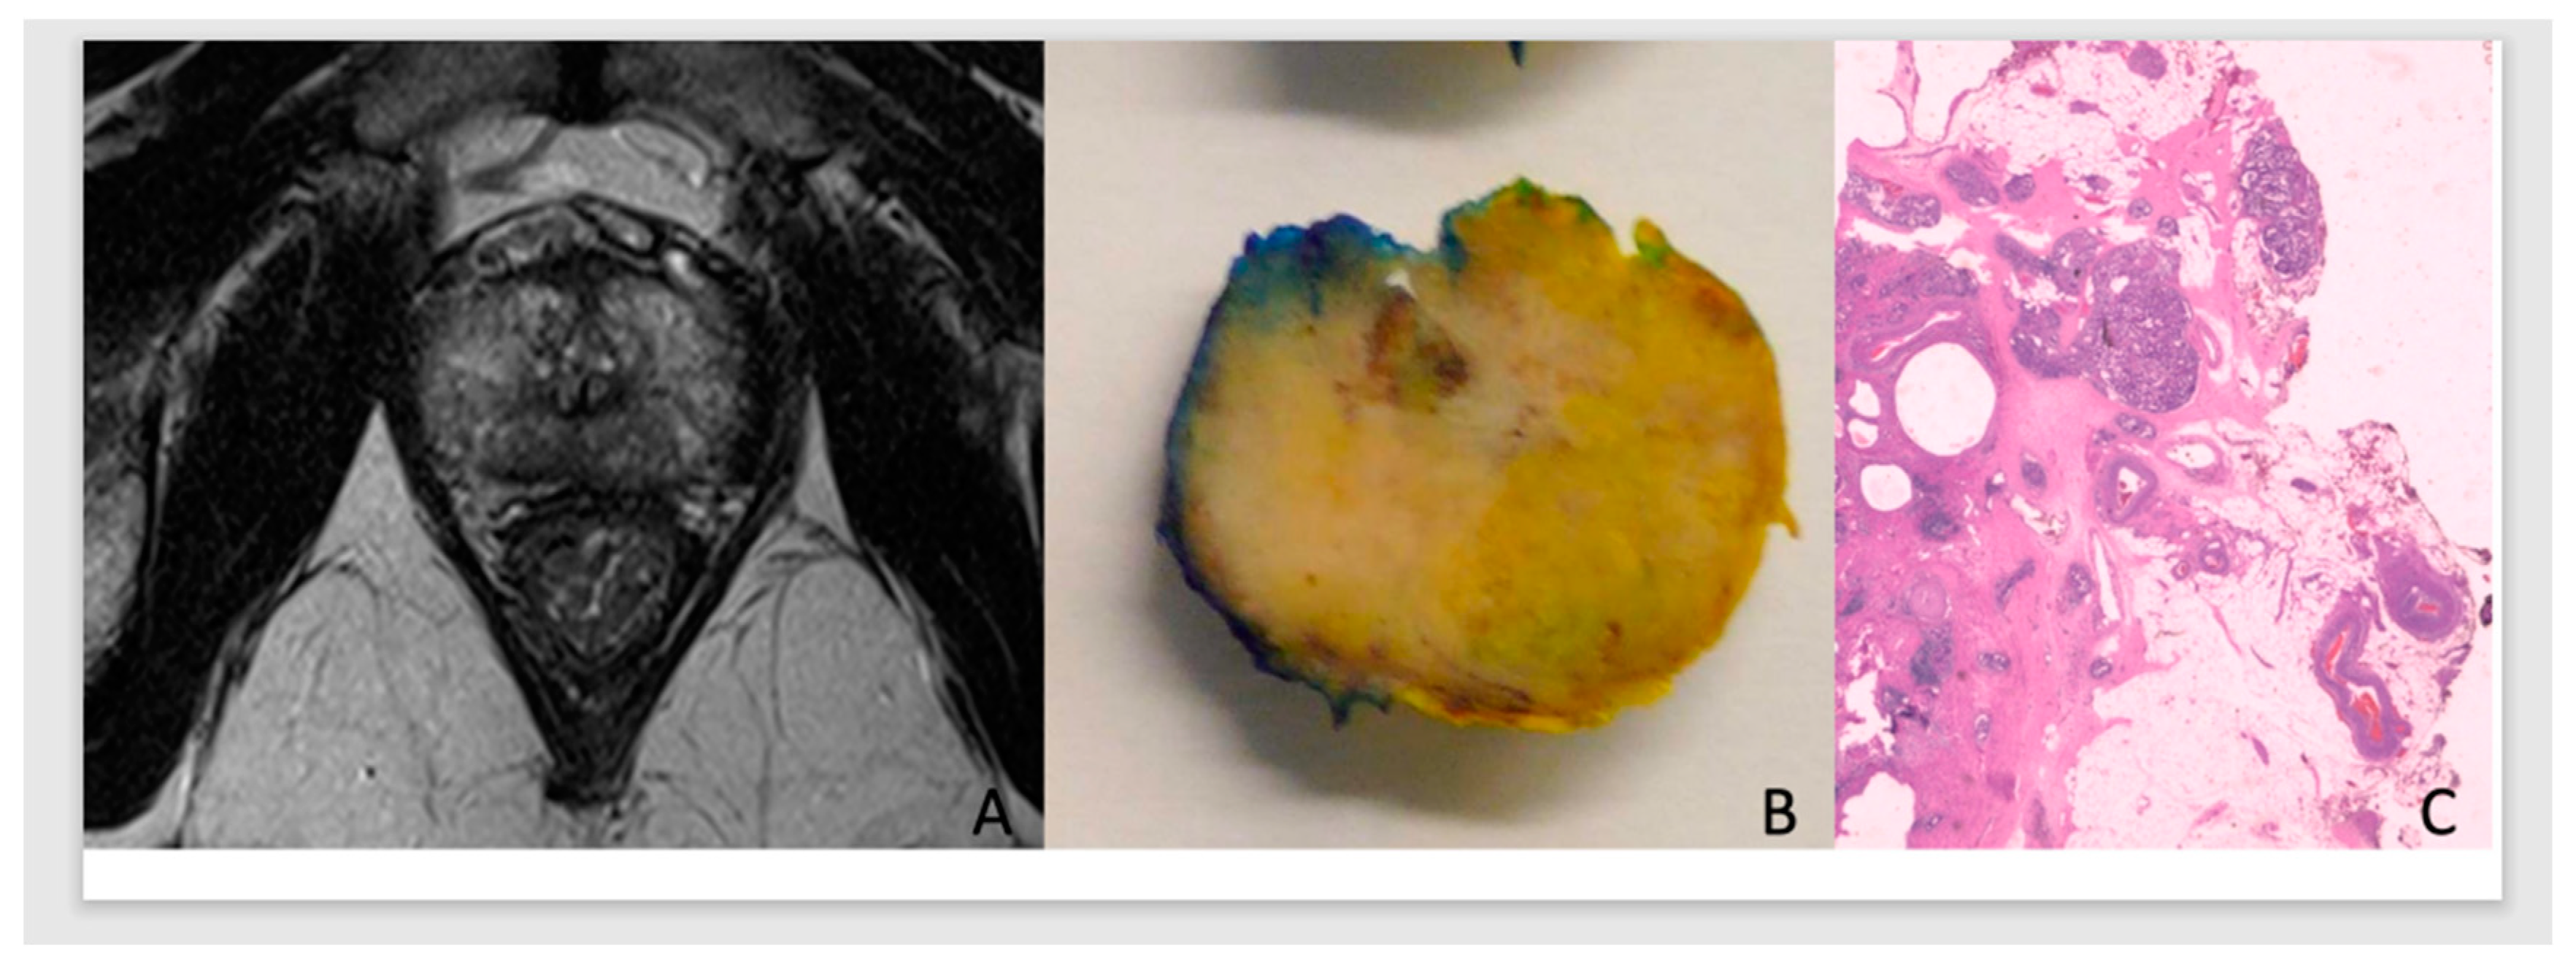

- In this predictive analysis, we added PCa pathological staging and surgical margins results of the prostate specimen [13]. Tumors were classified as pECE negative (pECE−) if no tumoral cells were detected on extracapsular tissue, and pECE positive (pECE+) if the presence of a tumoral extension beyond the periphery of the prostate gland was detected (Figure 1). Positive surgical margins (PSM) refer to the presence of tumor cells beyond the inked surgical margins of the resected tumor.

Figure 1. Illustration of the MRI, anatomical, and histology of PCa. ADC prostate G7(3+4)/Grade Group 2, in the apex with low signal on T2WI, high TCCL, and budging on MRI (A) on the right apex in the anatomic specimen (B), with pECE+ on histology (C).